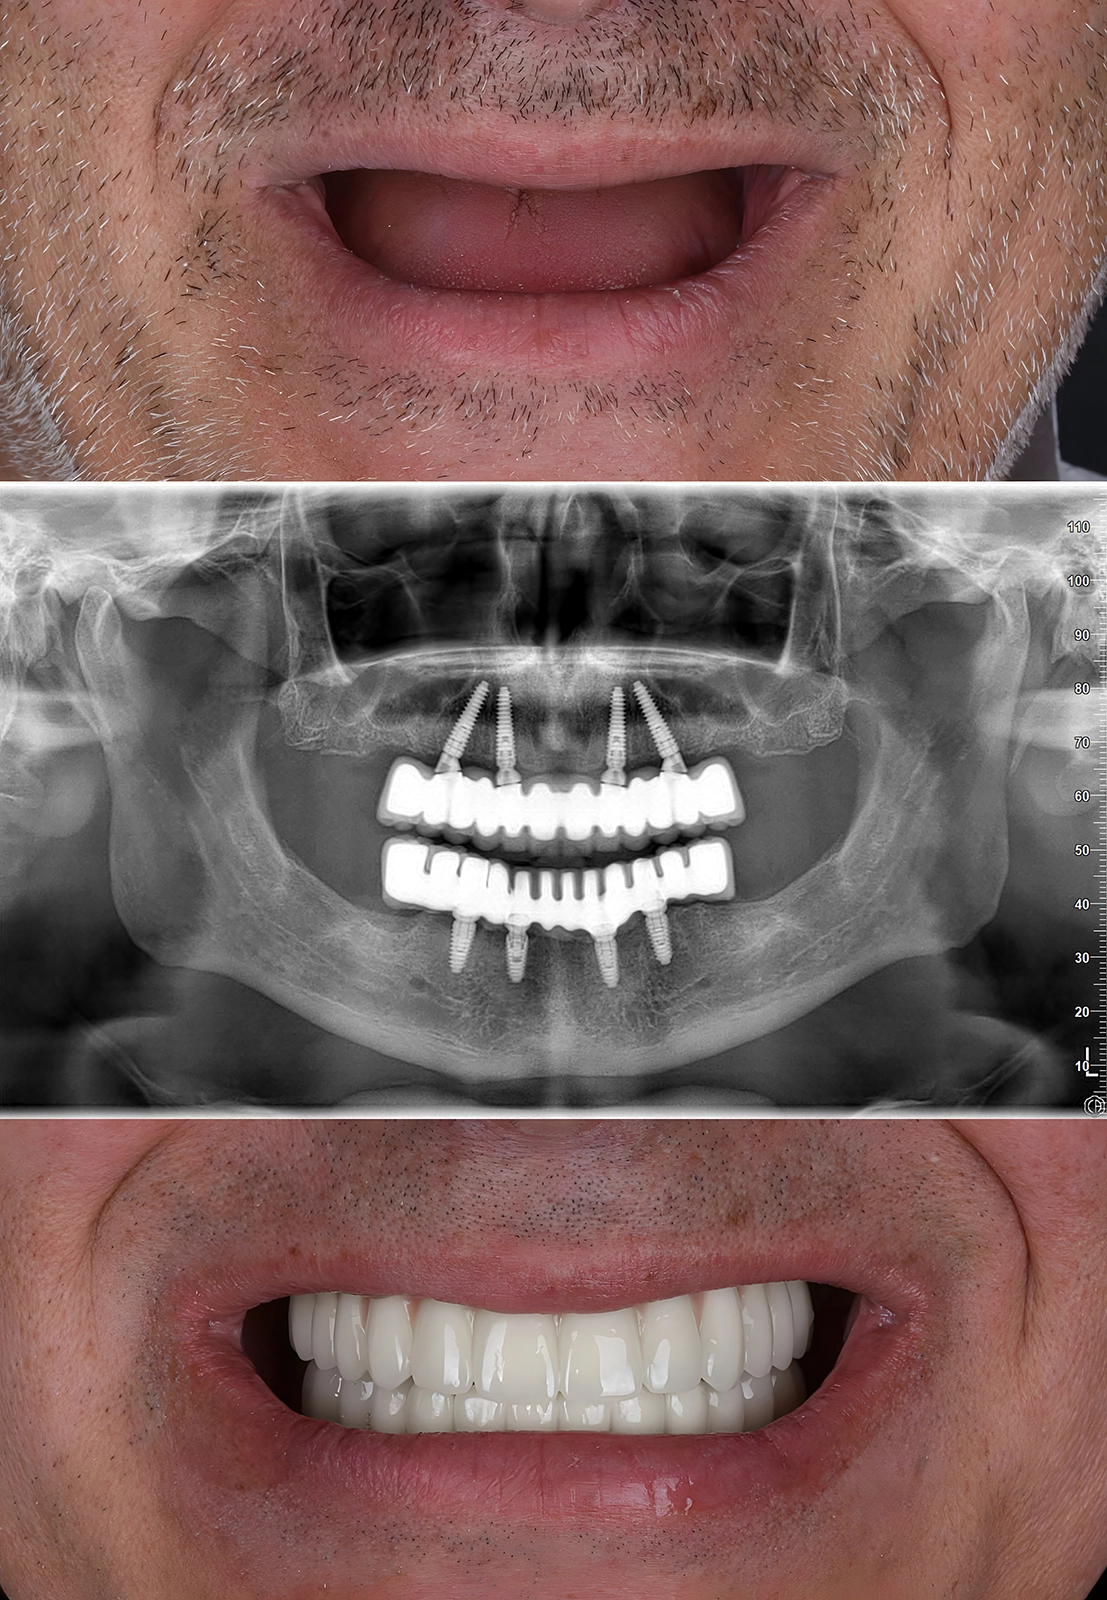

All-on-4 e All-on-6

Le tecniche All-on-4 e All-on-6 rappresentano soluzioni moderne, sicure e durature per chi ha perso tutti i denti di un’arcata. In un’unica seduta chirurgica, vengono inseriti 4 o 6 impianti dentali strategicamente posizionati, sui quali viene fissata una protesi fissa che restituisce funzionalità e sorriso.

Questo tipo di riabilitazione permette di tornare a mangiare, parlare e sorridere con naturalezza già dopo poche ore dall’intervento. Ogni trattamento è personalizzato sulle esigenze cliniche ed estetiche del paziente, con un’attenzione particolare al comfort, alla qualità dei materiali e alla rapidità di esecuzione, per offrire un’esperienza serena anche a chi viene da lontano.

Le tecniche All-on-4 e All-on-6 sono soluzioni implantari avanzate per riabilitare un’intera arcata dentale (superiore o inferiore) in modo fisso. Consistono nell’inserimento rispettivamente di 4 o 6 impianti dentali su cui viene ancorata una protesi fissa, restituendo al paziente funzionalità, estetica e benessere.

Dopo una visita specialistica e una pianificazione digitale, si procede con un unico intervento chirurgico, in anestesia locale o sedazione cosciente. Gli impianti vengono posizionati in modo strategico per garantire stabilità e durata nel tempo. Nella maggior parte dei casi, è possibile applicare una protesi provvisoria fissa entro 24 ore, permettendo al paziente di tornare subito a sorridere e a mangiare cibi morbidi.

Tempi e fasi del percorso

Il percorso completo può durare dai 4 ai 6 mesi, includendo la fase iniziale con la protesi provvisoria e quella finale con la protesi definitiva in ceramica o zirconia, progettata su misura. Il nostro team organizza ogni fase nei minimi dettagli, ottimizzando i tempi per chi viaggia da fuori, con programmi personalizzati e assistenza continua.

Risultati